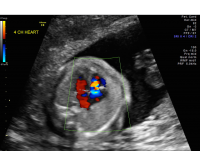

Ebstein’s anomaly is an abnormality in the tricuspid valve (the heart valve that connects the right atrium with the right ventricle). This abnormality may cause the valve to leak, resulting in enlargement of the right atrium. Right atrial enlargement can lead to problems including arrhythmia and poor lung development. Ebstein’s anomaly occurs in one in 10,000 live births.